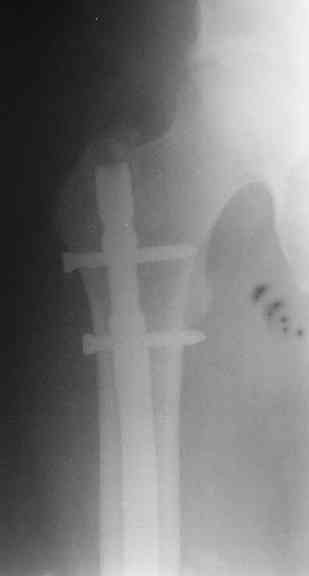

> денамизация - февраль 2006. ( 3 и 4 снимки) на сегодняшний день (снимок 5) беспокоит боли в тбс...

Судя по уровню перелома, винты в шейку избыточны, подойдет и диафизарный гвоздь. Все, что нужно, это тиски и труба. Загнуть сразу ниже отверстий градусов на 8-10, и вся недолга. Последние годы у нас это рутинная практика. Предызогнутые еще с завода гвозди неудобны тем, что они уже правый-левый.

Согласен, что 3,5 см укорочение этим снимкам не соответствует, за счет перелома и деформации - 1,5 см от силы. То есть либо ошибка измерения, либо приводящая контрактура, либо укорочение за счет другого отдела.

Согласен, что закрытый реостеосинтез с рассверливанием и коррекцией оси - это то, что надо. Мы бы ввели в центральный отломок статических 2-3 винта, и один динамический винт в дистальном отломке.